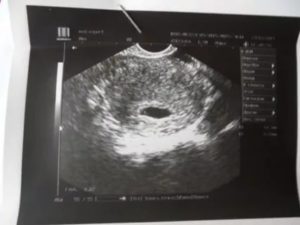

Возможно, это вас убедит, но уже несколько другую картинку увидит врач, если у вас 5 недель, 5 дней беременности. УЗИ может быть более информативным, На шестой неделе врач уже точно должен обнаружить плодное яйцо в полости матки. В плодном яйце четко определяется желточный мешочек.

Размер эмбриона составляет уже 6-19 мм, и до того, как начнут работать его собственные внутренние органы, ткани желточного мешочка выполняют все обменные функции. При этом размер его не должен быть около 6 мм. На шестой неделе врач уже должен увидеть белое кольцо, это будущая плацента.